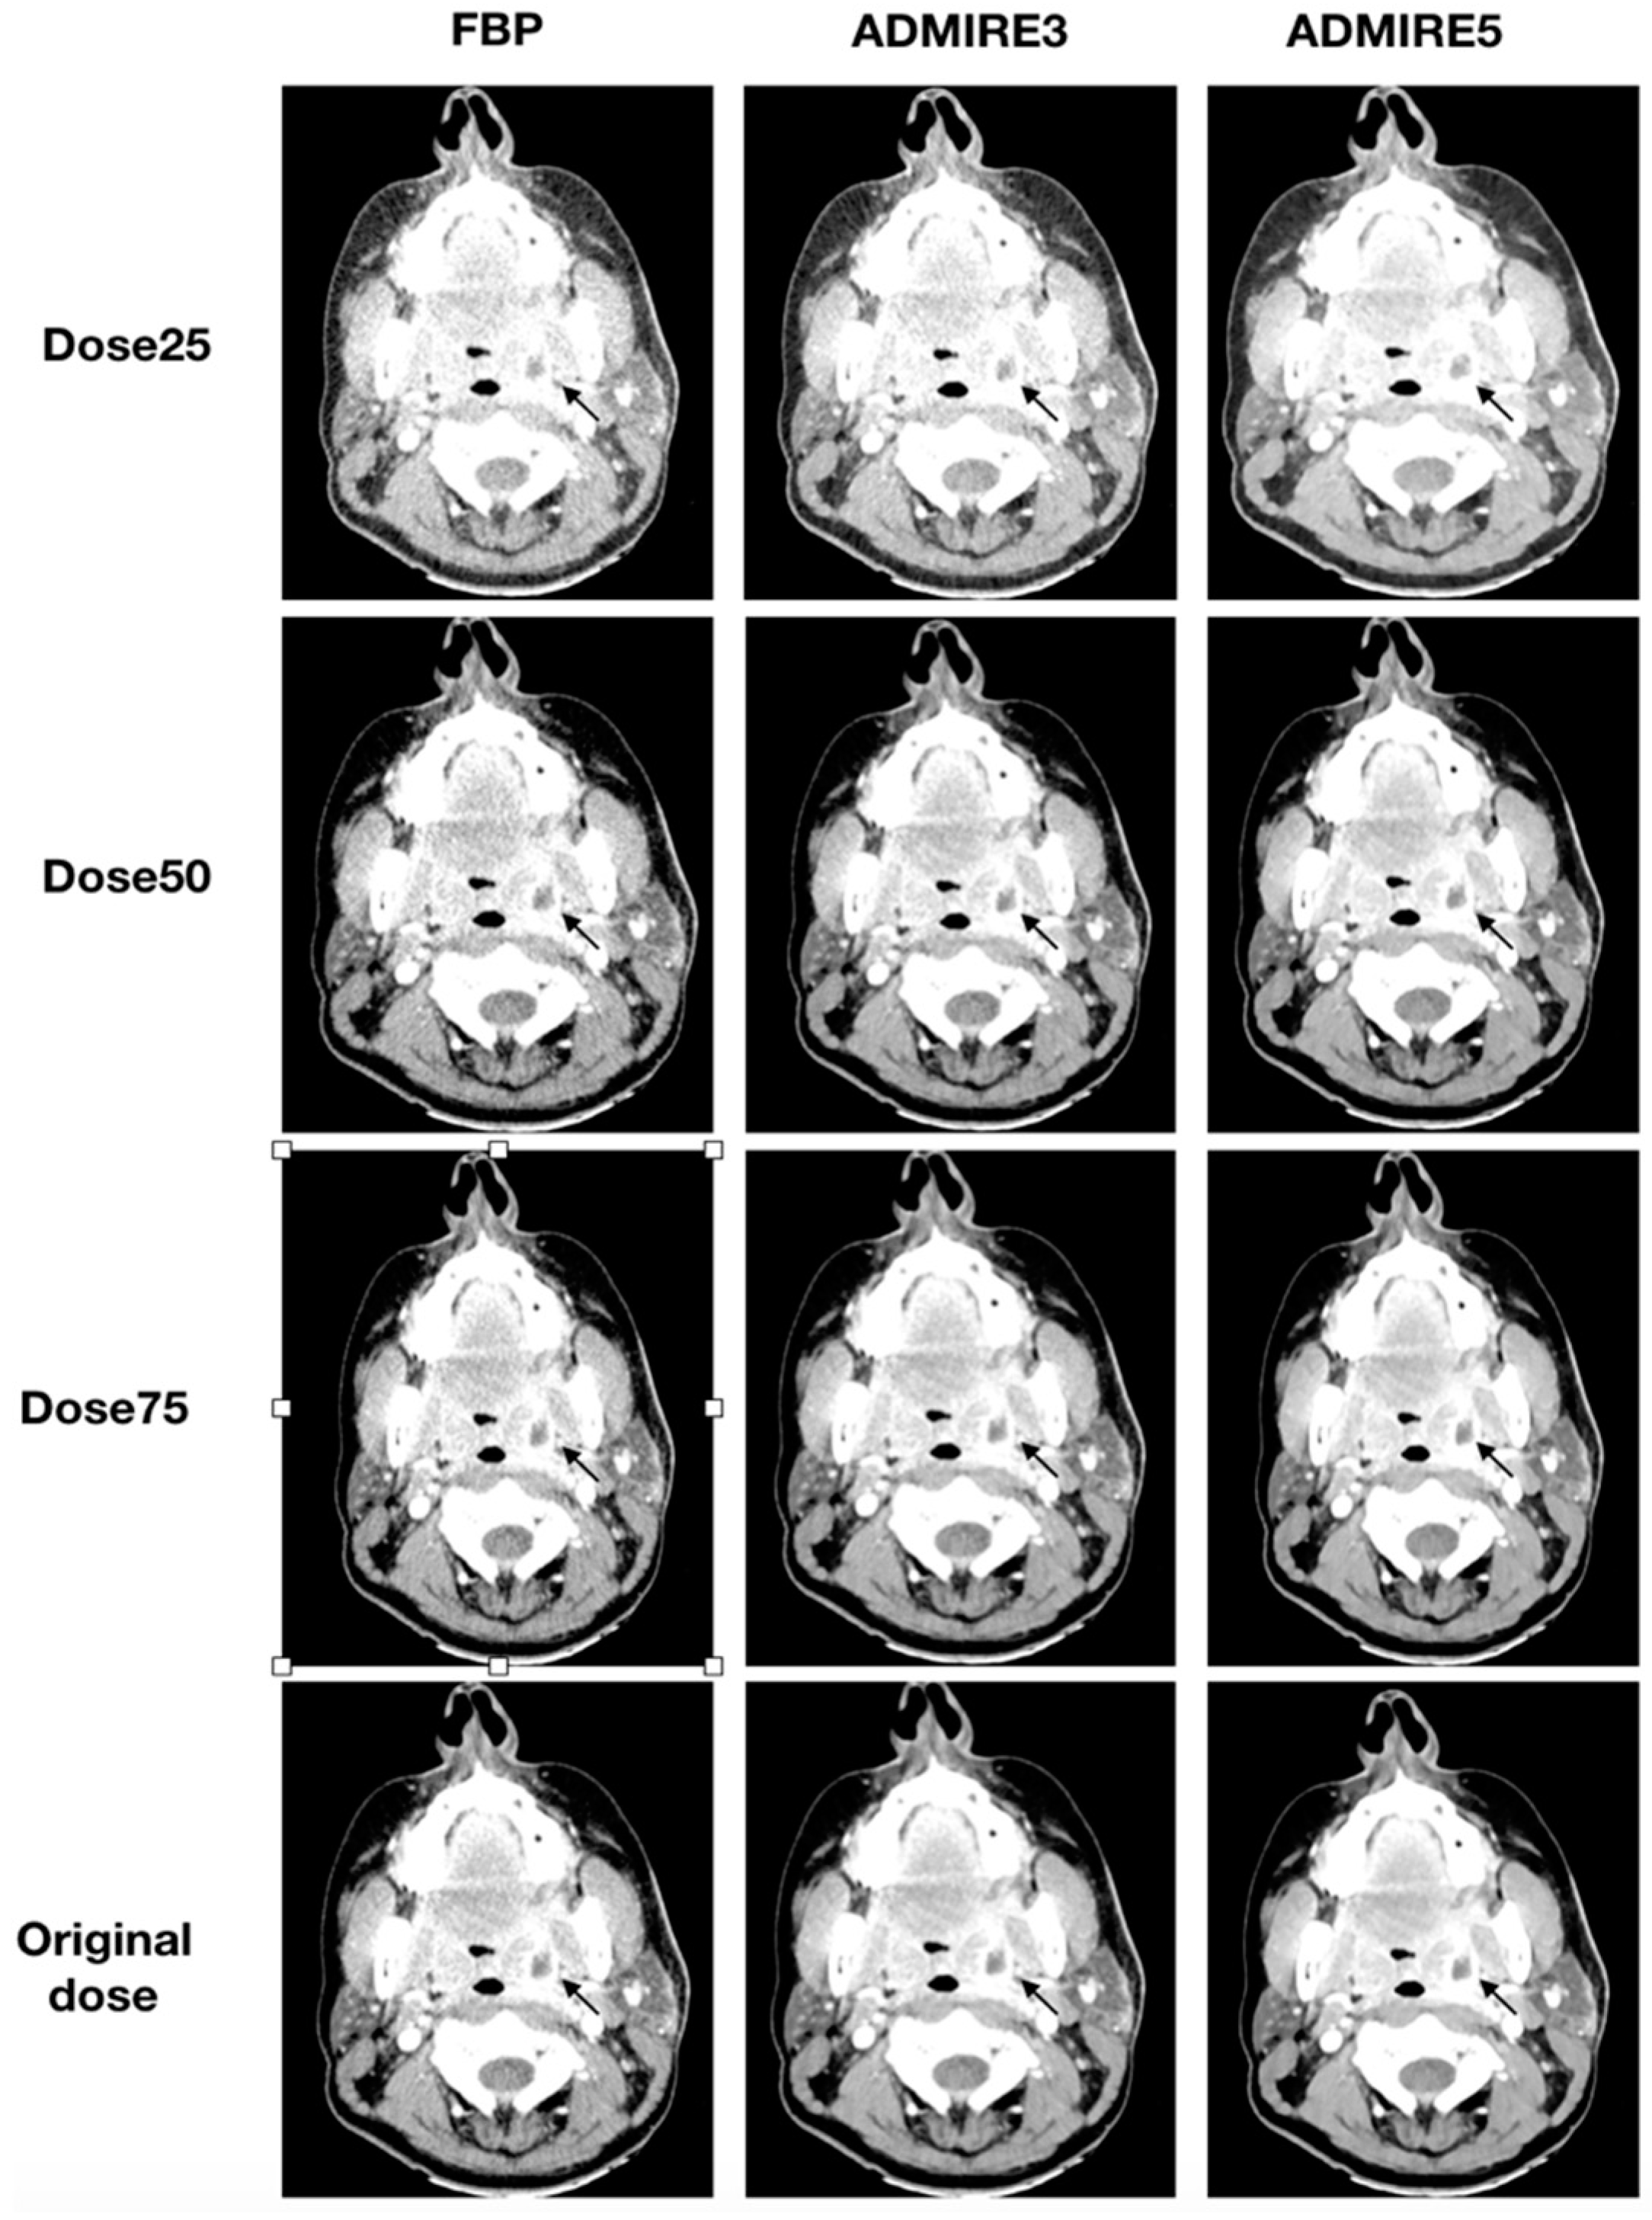

All 48 patients were analyzed for the presence of a neck abscess. A total of 35 abscesses were diagnosed in the original datasets. All three blinded readers had a sensitivity of 100% (95% CI: 88–100) and specificity of 100% (95% CI: 72–100) for all simulated low-dose datasets, which were iteratively reconstructed with ADMIRE 3 or ADMIRE 5. FBP datasets had a sensitivity of 100% (95% CI: 88–100) and a specificity of 100% (95% CI: 72–100) for a dose reduction to 50% of the original dose. Deviations were only found in FBP reconstructed datasets at a dose of 25% of the original dose. Illustrations of the different reconstructions at the respective dose levels are shown in Figure 5 and Figure 6.

Figure 6.

Axial tomographic slices of a 46 year old female patient with left-sided peritonsillar abscess (arrow). All images were reconstructed with FBP, ADMIRE 3, and ADMIRE 5 (from left to right) at 75%, 50%, and 25% dose reduction of the original dose. Reader 1 missed the abscess in reconstruction mode FBP at a dose of 25%.

For FBP datasets at a dose reduction of 25% of the original dose, Reader 1 had a sensitivity of 88.6% (95% CI: 72–96) and a specificity of 92.3 (95% CI: 62–99). Ratings revealed one false-positive case and four false-negative cases, resulting in a positive predictive value (PPV) of 96.9% (95% CI: 82–99) and a negative predictive value (NPV) of 75% (95% CI: 47–91). Reader 2 had three false-negative cases and no false-positive case, resulting in a sensitivity of 91.4% (95% CI: 76–98) and a specificity of 100% (95% CI: 72–100) and a PPV of 100% (95% CI: 87–100) and NPV of 81.3% (95% CI: 54–95). Reader 3 had two false-negative cases and no false-positive case, resulting in a sensitivity of 94.3% (95% CI: 80–99) and a specificity of 100% (95% CI: 72–100) and a PPV of 100% (95% CI: 87–100) and NPV of 86.7% (95% CI: 58–98). Results for FBP at a dose reduction of 25% of the original dose are shown in Table 3.